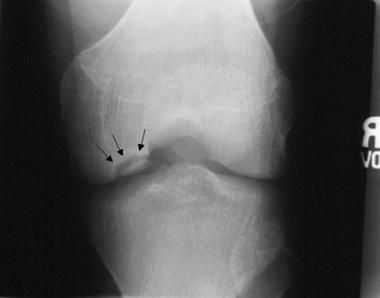

Нарушение биомеханики сустава из-за асептического некроза субхондральной кости и наличие свободных тел внутри сустава приводят к развитию деформирующего гонартроза. Его первым клиническим симптомом является боль, усиливающаяся при физической нагрузке, хромота, особенно при спуске по лестнице. Пациенты отмечают "блоки" коленного сустава и чувство инородного тела в нём. На рентгенограммах можно обнаружить сужение суставной щели, внутрисуставные тела и остеосклероз.

В более тяжёлых стадиях болезни пациент не может до конца выпрямить или согнуть ногу в колене, его беспокоят резко выраженные боли и хромота, а конечности деформируются во внешнюю или внутреннюю сторону. На рентгенограмме суставные поверхности значительно деформированы и склерозированы, отмечается субхондральный некроз, суставной щели практически нет, костные разрастания становятся обширными, появляются свободные суставные тела.

Инструментальная диагностика начинается с рентгенографии сустава в прямой и боковой проекциях, а также в специальных укладках — рентгенография в заднепередней проекции при сгибании в колене до 45 ° и аксиальная (осевая) рентгенограмма надколеннико-бедренного сустава. Рекомендуется проводить рентгенографию обоих коленных суставов, если даже признаки нарушения наблюдаются только в одном, так как в практике около 25 % случаев приходится на билатеральное поражения суставов.

Также необходимо проводить билатеральную полноразмерную рентгенографию нижних конечностей, потому как их оси могут быть связаны с локализацией рассекающего остеохондрита и влиять на методы и успешность лечения.